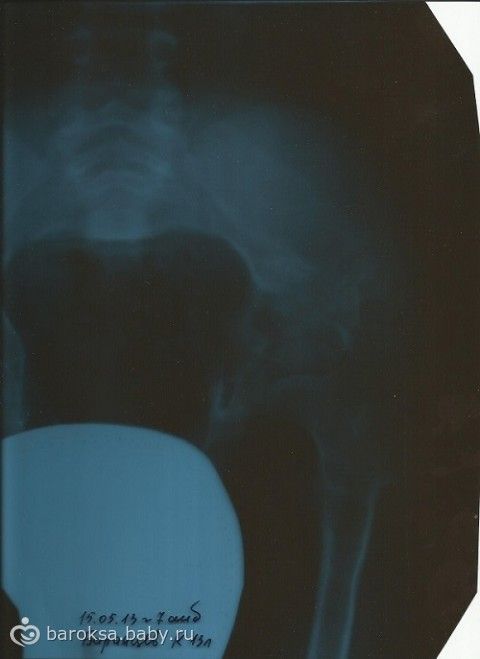

Новости у нас не очень хорошие. Получила новые снимки т/б суставов, которые делали на прошлой неделе. Прочитала описание, и… руки опустились. Сращение, на месте операции, до сих пор не завершилось. Появился остеопороз костей и не понятно, откуда взявшийся перелом. Как такое может быть? Ведь мы очень ответственно выполняем все назначения и рекомендации — делаем все, чтобы получить хороший результат. Очень надеялась, что все идет к завершению и Костюхе, в этот раз, обязательно разрешат вставать на ножки и постепенно начинать учиться ходить.

Созвонились с нашим врачом-ортопедом, записались на прием. Во вторник съездили. Диагноз прежний, в динамике медленное ухудшение. Я уже думала, что в Евпаторию мы не поедем. Но доктор сказала, ехать обязательно!!! И дала свои рекомендации по лечению — провести этапное гипсование, дельфины — замечательно, как можно больше времени проводить в воде. Остальное, все как обычно — грязи, ванны, лфк и так далее. На данный момент, Евпатория, это практически единственное место, которое подходит Косте в плане лечения. Грязи — для сращения и укрепления костей, вода — расслабляет, плюс гипсование, хорошее лфк и другие полезные процедуры. Единственное, что отменили, это уколы «Цереброкурина». Вместо них, назначен курс «Нейробиона».На поездку истрачено 1800 рублей, на такси.